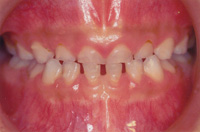

又、最近主流の考え方として、アーリートリートメントといって、永久歯の生えそろう永久歯列期が完成する前段階から医学的な介入を行い歯並びや咬み合わせが正しくなるよう管理・指導していくことで、将来大掛かりな矯正治療を避けられるようになりました。

ムーシールド(小児矯正)

幼少期の反対咬合(受け口)は自然治療が見込まれますが、2歳で反対咬合だったお子様の50%は自然治癒する一方で、3歳になると、自然治癒率は6%まで低下すると言われています。つまり、反対咬合は3歳より治療適応となります。従来の矯正治療では低年齢児に対応出来る治療法はごくわずかに過ぎず、大人の歯に全部生え変わったら矯正治療で治しましょうと言って、その時期まで何もしないという考え方が主流でした。

現在では、アーリートリートメントといって、早期治療によって将来予測される症状を少しでも軽くし、良い方向へ修正して行く、という考え方が確立されています。

例えば、叢生(でこぼこした歯並びの乱杭歯)の矯正治療の場合はある程度永久歯が生えそろう10歳程度まで様子を観察しますが、反対咬合の場合は放置しておくとかえって悪い状態になってしまうことが予測されるため、その事実を御説明し、早めの対処をお薦めしております。特に反対咬合は大人になると大きな審美障害を来たし、それからでは大掛かりな治療(下顎の骨を切る手術)をしなければ改善は難しくなってしまいます。

ムーシールドは就寝中にマウスピース型の矯正装置をくわえるだけという簡便さで、幼いお子様に対しても非常に少ない負担で応用出来ます。上口唇圧を排除し、口唇圧のバランスを整え、低位舌を改善し、逆被蓋の改善を促します。使用期間は1年間で、就寝時に装着させるか、日中2時間以上装着させて下さい。その後、定期的な経過観察が必要です。

適応年齢はムーシールドSサイズが乳歯列期のお子様(3~5歳)、ムーシールドMサイズが混合歯列期のお子様(6~11歳)となっており極端な反対咬合のお子様(反対咬合のうち5%程度)は、その後本格的な矯正治療が必要な症例もございますので、御了承下さい。